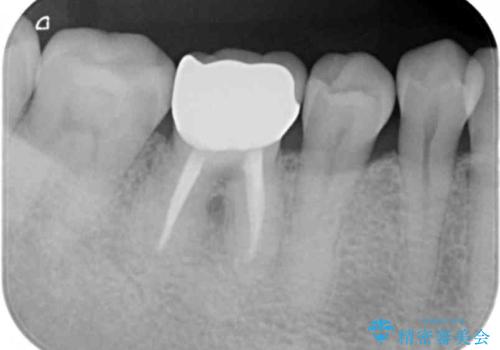

目立っていた銀歯が自然な白い歯となり、長年のコンプレックスが解消されたと満足いただくことができました。

- 13.2万円(ジルコニアクラウン・仮歯)7.7万円(セラミックインレー)費用は治療当時の料金となります